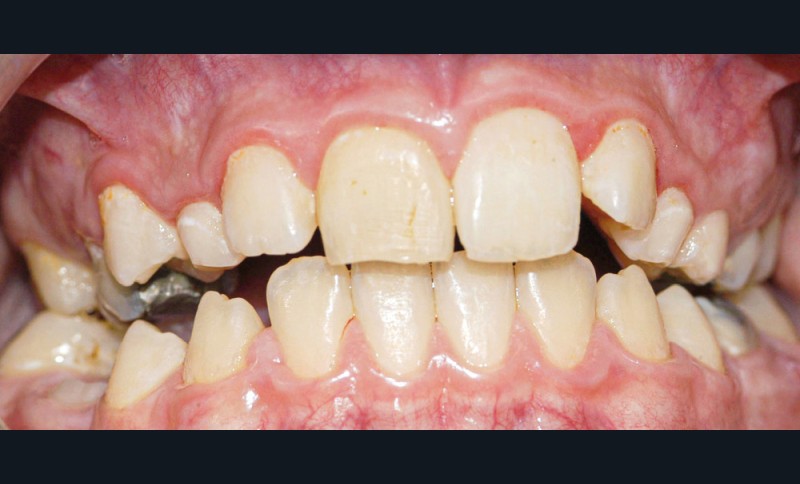

Cas 2

Adolescente de 17 ans ayant trois dents (12, 11, 21) expulsées lors de travaux aux champs (fig. 5), ainsi qu’une luxation latérale de la 13. Elle est adressée par les urgences du CHU de Rennes et la consultation a lieu 6 heures…